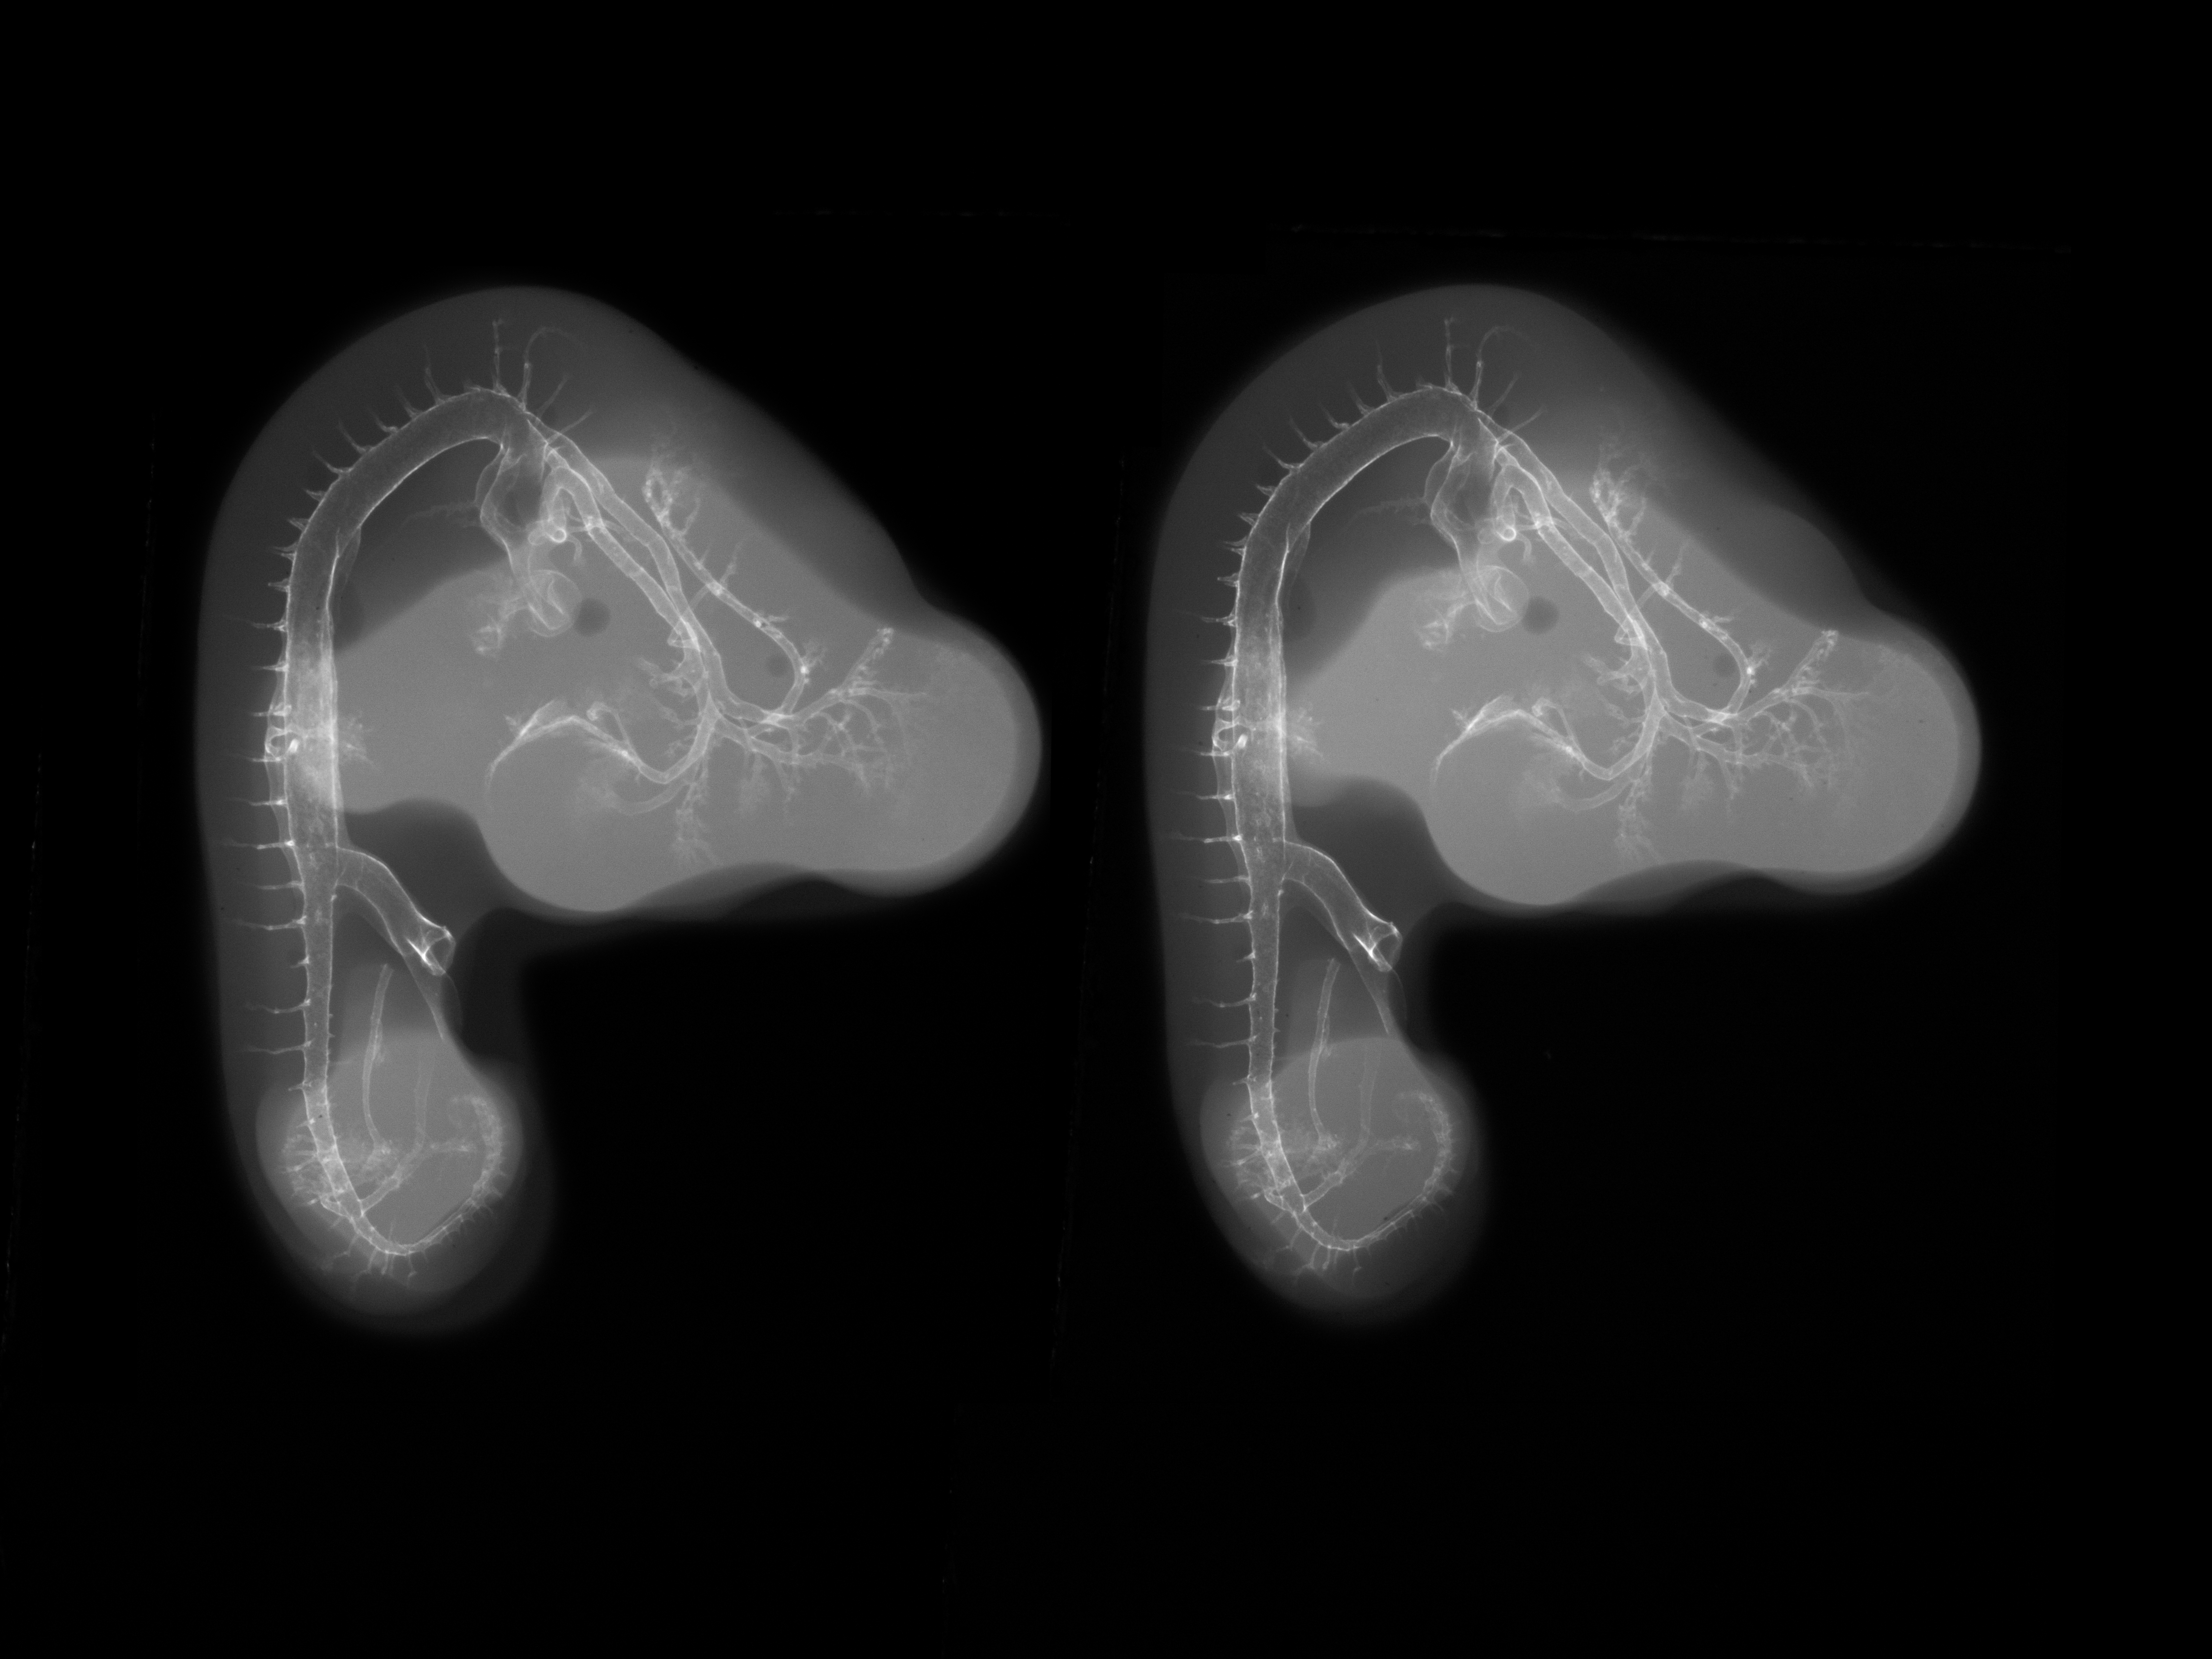

Stereo X-Ray Micrographs